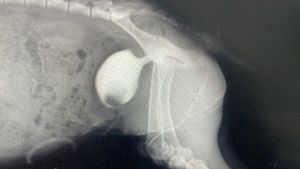

Torinho desenvolveu cálculos urinários,  sendo que um desses obstruiu completamente a saída da urina da bexiga para a uretra. Fazendo com que sua bexiga quase se rompesse.

Rapidamente levamos ele para o Hospital de Ruminantes da UFMG,  e prontamente foi atendido,  submetido a vários exames, internado e operado. Em uma mesma noite passou por 2 cirurgias.  E hoje ainda está internado, com duas sondas fixas, uma na uretra e a outra ligando a bexiga ao meio externo. E está em recuperação para passar por uma terceira cirurgia,  afim de dar a ele expectativa e qualidade de vida. Provavelmente terá que usar sonda e fraldas pelo resto de sua vida.